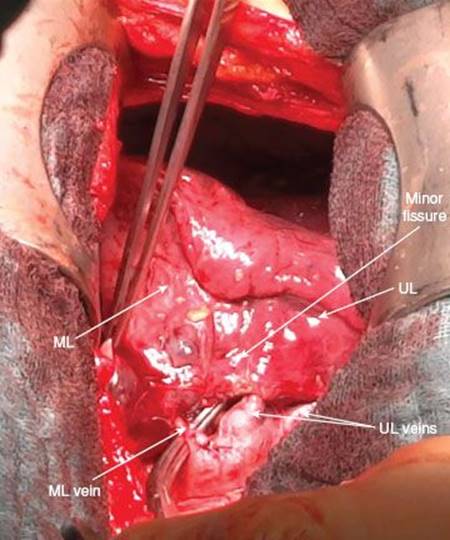

However, as there are mostly more than one middle lobe arteries, complete visualization of all arterial branches is recommended. Therefore, the middle lobe is now placed anteriorly exposing the major fissure.

Dissection in the interlobium (Fig. 11.8) will lead to the interlobar part of the pulmonary artery which is usually found at the confluence of the major and minor fissures. The visceral pleura is held up with a DeBakey forceps and incised by electrocautery or Metzenbaum scissors. In this area there is rarely a complete bridging of lung parenchyma, so dissection can be carried down to the artery which presents itself again as a yellowish structure. Here, lymph nodes of station 11 are lying on top of the interlobar artery and as soon as they are lifted up the wall of the vessel becomes visible.

Resection of lymph nodes in the interlobium is often necessary before the artery and the whole vascular situation is clearly understood. Once the visible wall of the interlobar artery is completely freed from surrounding tissue, further dissection upward (centrally) with the scissors or bluntly with the small sponge stick will identify further lymph nodes next to the branches of the middle lobe arteries. Lymph nodes are again gently grasped at their capsule and dissected from the arterial wall. Removal of the lymphatic tissue off the arterial branches is performed over a distance of 0.6 to 1 cm to allow easy and safe closure of the vessel. It also enables the vessel to stretch if further manipulation is performed at the level of the interlobar artery. This might be necessary if there are two separate arteries to the middle lobe when only the distal branch may be encountered from the interlobium.